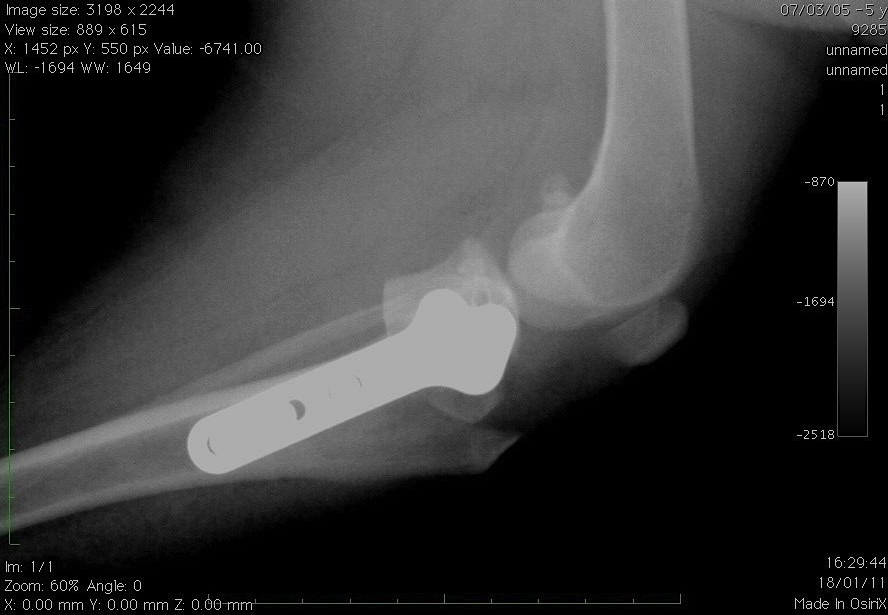

- Die Behandlung von Pathologien der Ellbogen Oder von die Schulter (Ellbogendysplasie, Osteochondritis der Schulter usw.).